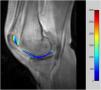

De las imágenes seriadas obtenidas rápidamente tras administrar un medio de contraste en bolo se analiza el comportamiento de la captación tisular a partir de la entrada arterial. Mediante cálculos y ajustes matemáticos se obtienen los parámetros farmacocinéticos tisulares de la permeabilidad vascular desde el vaso (Ktrans) (fig. 3), la fracción de volumen de intercambio del intersticio (ve), el coeficiente de extracción del intersticio al vaso y la fracción de volumen sanguíneo intercambiable.

Hay estudios que demuestran la relación entre el aumento de estos parámetros y un mayor grado de degeneración del cartílago articular. Así, se ha demostrado que hay diferencias estadísticamente significativas entre el cartílago normal, la condromalacia y la artrosis para Ktrans y ve, con aumentos muy significativos conforme la enfermedad progresa (fig. 4). Los valores son, además, reproducibles con valores de variación inferiores al 15% para equipos de 1,5 T10 e incluso menores para equipos de mayor intensidad de campo11.